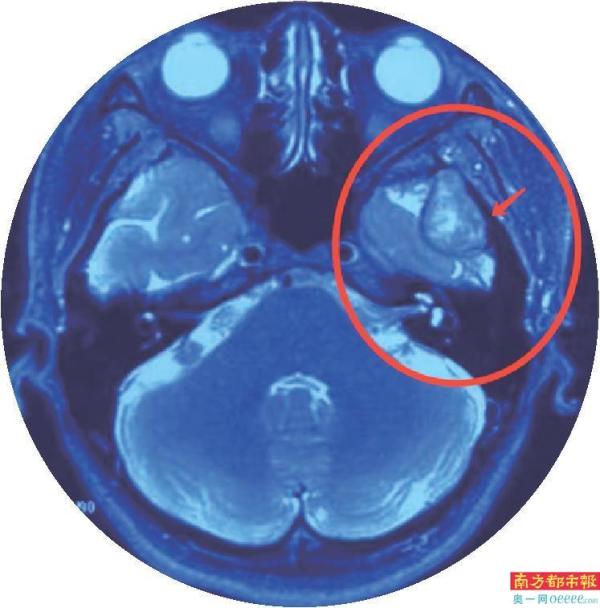

MRI提示:肿瘤已经侵入颅内。

最可怕的是,脸上凸起的肿物只有3cm左右,但是,肿瘤一直往深处发展已经侵蚀到颅底,大概有6×4cm的大小!

“花姐的这个肿瘤是发生在腮腺深叶并向颅内发展的罕见巨大肿瘤,其实腮腺肿瘤并不罕见,但是瘤体巨大,增长较快且侵蚀入颅内的实属罕见。并且这种肿瘤难以发现,早期没有明显的症状与不适,部分患者会出现面部不对称、面瘫(口角歪斜、闭眼不全等)等症状,容易复发甚至恶变,需要尽快手术去除。”张国权主任表示。